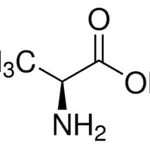

Merck Sigma의 ALANINE은 생화학 및 세포 배양 연구에 사용되는 고순도 아미노산 시약입니다. 안정적인 품질로 2–8°C에서 보관하며, 분자식은 C3H7NO2, 분자량은 89.09입니다. CAS 번호 56-41-7로 등록되어 있습니다.

Merck Sigma에서 공급하는 고순도 알라닌(Amino Acid) 시약으로, 생화학 및 분자생물학 연구용으로 적합합니다.

ALANINE은 단백질 구성 아미노산 중 하나로, 다양한 생화학적 실험 및 연구에 활용됩니다.

| Molecular Formula (분자식) | C3H7NO2 |

| Molecular Weight (분자질량) | 89.09 |